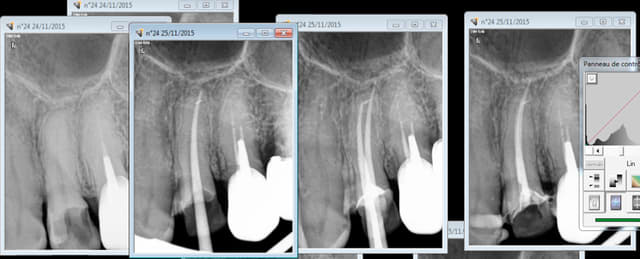

Capture d e cran 2015 11 24 23.14 - Eugenol

Capture d e cran 2015 11 24 23.26 - Eugenol

Tu dis rien en général, il ne se passe rien. C'est un aléa thérapeutique. Tu surveilles l'évolution éventuelle. Un apex en crochet par exemple ca arrive et à tout le monde endos exclusifs inclus ( moins peut etre parce qu'ils prennent leur temps et qu'ils font ca toute la journée)

Je paye une caisse de champagne à l'endo exclusif qui va me retirer ca par voie orthograde.-)))

Ca c'est à cause du localisateur d'apex, j'y étais mais ce con me disait que j'y étais pas tu insistes et paf. ( il a merdé sur l'autre canal d'ailleurs dépassement de 2 mm cone radio coupé de 2mm)

Capture d e cran 2015 11 25 13.18 - Eugenol

Jolie l'endo sous la 15 (ou 25): pas de cône, incomplète, 5mn avec une simple pate et un lentullo, la couronne semble être là depuis longtemps, aucune image radio périapicale, tout va bien

Et tu stresses pour une endo monocanale facile mais consciencieuse...